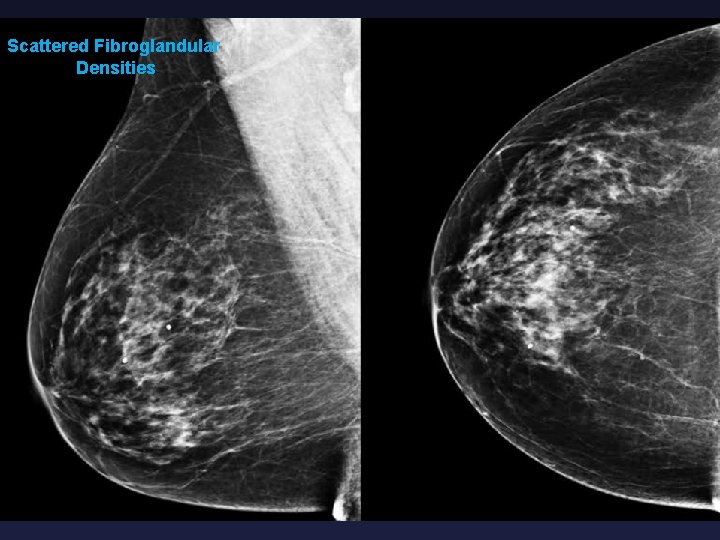

Controversies in Screening Mammography RISKS § False negative exam (“Happy Gram”) § Increased breast density makes mammographic detection of malignancy more difficult § Breast density = proportion of fat to gland § Almost entirely fatty § Scattered fibroglandular densities § Heterogeneously dense which may obscure small masses § Extremely dense

Scattered Fibroglandular Densities